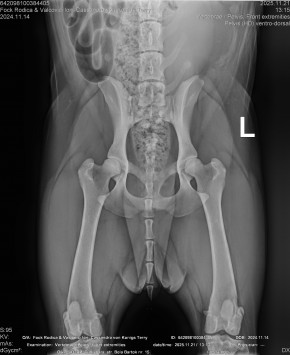

CASSANDRA VON KONIGS-TERRY

( CASSY )

Data nasterii:

14.11.2024

FOCK RODICA si VALCOVICI ION